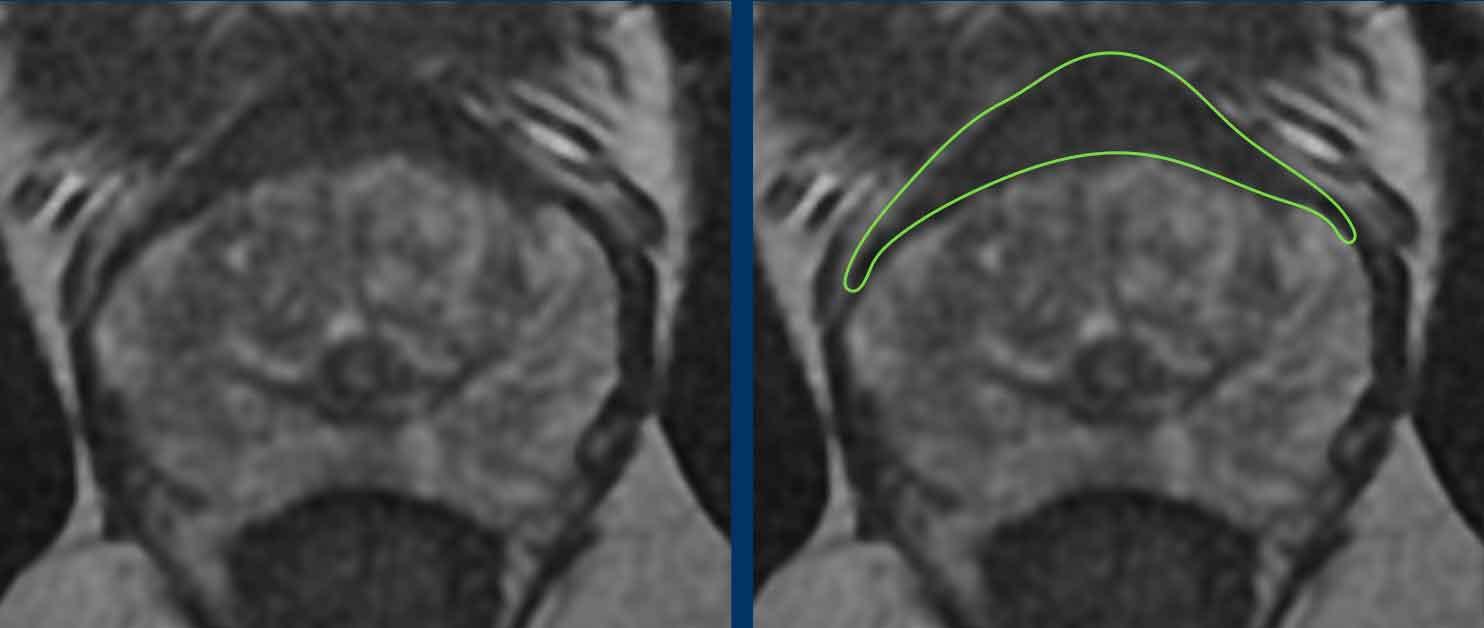

Có một tổn thương ở phần trước bên phải của vùng chuyển tiếp.

Tổn thương có bờ không đều trên chuỗi xung T2W (điểm 4) và giảm tín hiệu khu trú rõ rệt trên ADC (680 mm/s) (điểm 4), kích thước không vượt quá 15 mm.

Tổn thương này tương ứng với PI-RADS mức 4.

Sinh thiết dưới hướng dẫn kết hợp MRI-Siêu âm cho kết quả Gleason 3+4.

Tại vùng ngoại vi bên phải có một vùng giảm tín hiệu nhẹ hình nêm (điểm 2) không có đặc điểm nghi ngờ trên DWI/ADC (điểm 2).

Tổn thương được xếp loại PI-RADS mức 2. Vùng này lành tính và nhiều khả năng tương ứng với teo tuyến hoặc tổn thương viêm khu trú trên mô bệnh học.